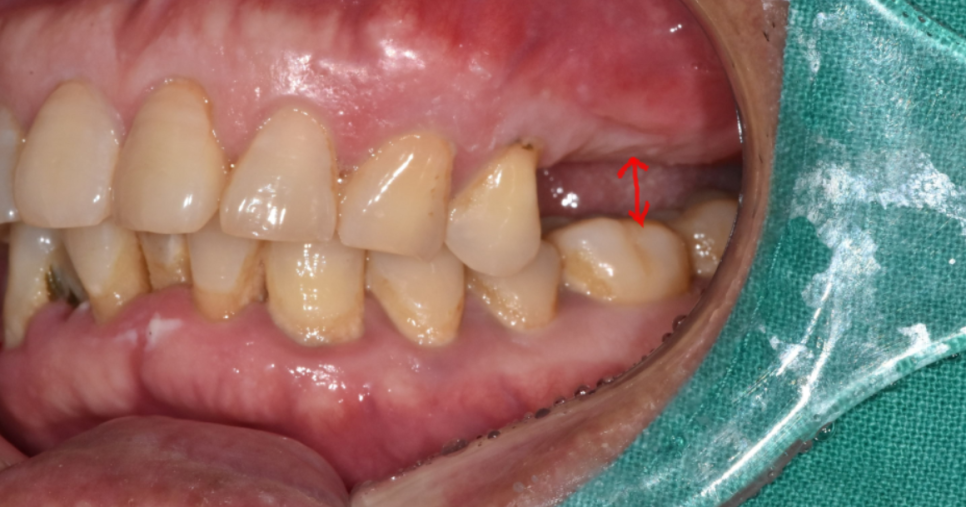

이번에는 위 아래로 변화 케이스입니다.

치아는 1개씩 서로 맞물리는 짝궁이 있는데

어느 한쪽이 빠져버리면

맞닿이는 치아가 없겠죠~?

그러다 보면 맞닿이던 방향으로

치아가 움직이게 됩니다.

이런 현상을 "치아 정출"이라 말합니다.

오늘 환자분처럼 위에 치아가 없는 경우 치아 올라옴

아래 치아가 없는 경우 위에 치아 내려감 현상이 생겨요.